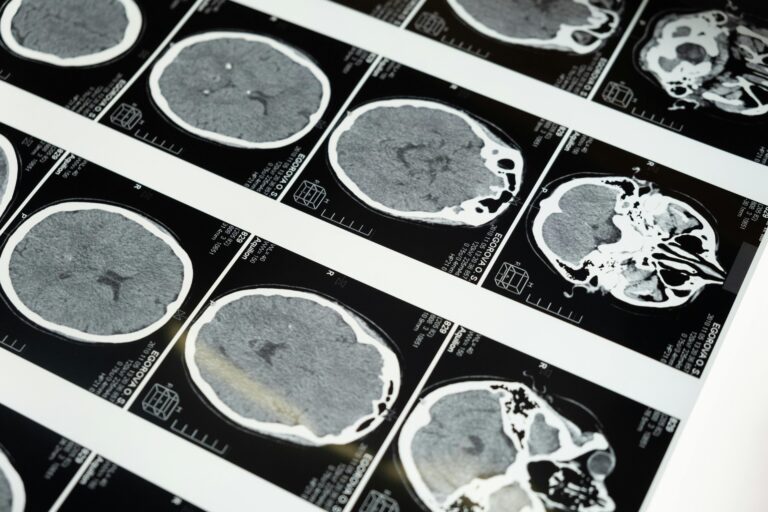

Advanced imaging for accurate diagnosis of complex health conditions

Fast and precise imaging for detailed cross-sectional views of the body

Fast and precise imaging for detailed cross-sectional views of the body

Advanced imaging for accurate diagnosis of complex health conditions

Advanced imaging for accurate diagnosis of complex health conditions

Fast and precise imaging for detailed cross-sectional views of the body

Fast and precise imaging for detailed cross-sectional views of the body

Advanced imaging for accurate diagnosis of complex health conditions

Advanced imaging for accurate diagnosis of complex health conditions

Fast and precise imaging for detailed cross-sectional views of the body

Fast and precise imaging for detailed cross-sectional views of the body

Advanced imaging for accurate diagnosis of complex health conditions